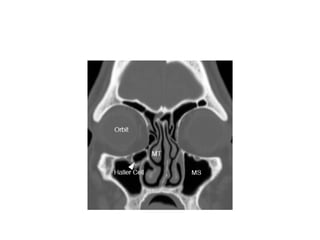

Haller cells

• Ethmoidal air cells belonging to the

anterior ethmoidal group.

• Also known as the infra orbital cells

• Adhere to roof of maxillary sinus forming

the lat wall of infundibulum

• Enlargement of these cells can impede

the maxillary sinus drainage

Paradoxical curvature- can potentially narrow or

obstruct the infundibulum or middle meatus.

bony septum in the maxillary

sinuses (MS)